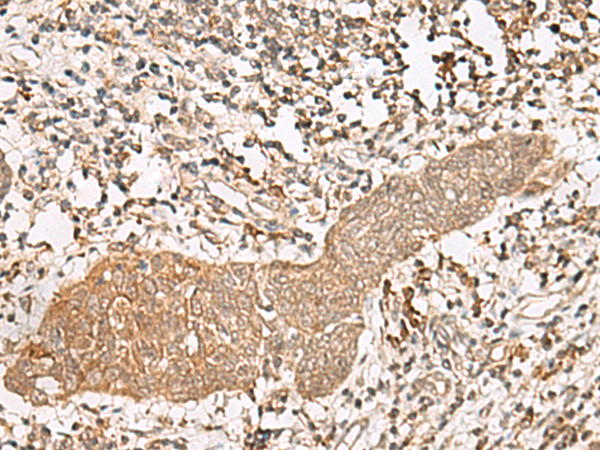

IHC positive control: |

Human esophagus cancer and Human thyroid cancer |

IHC Recommend dilution: |

40-200 |